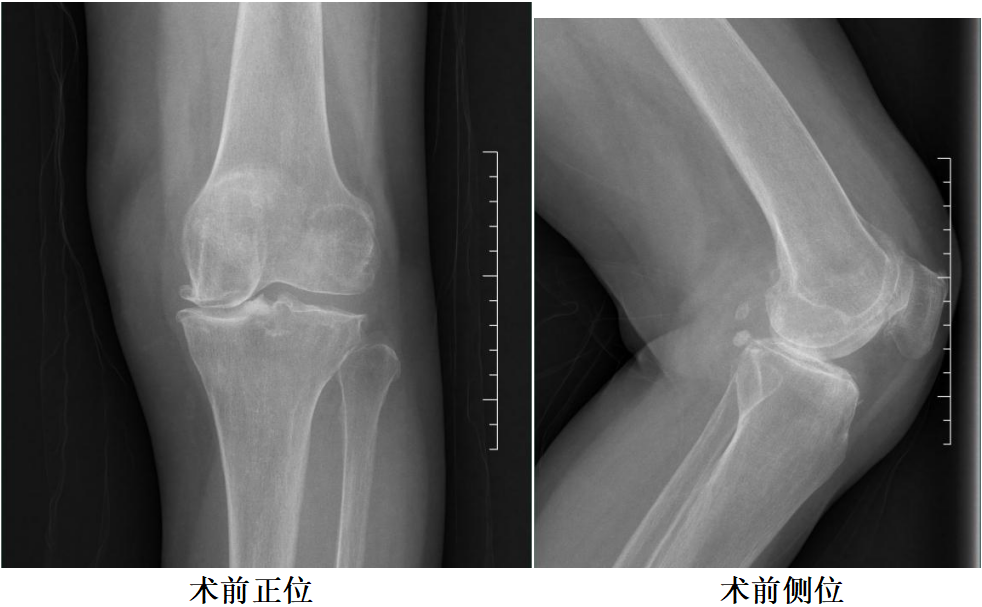

女性患者,69 岁,左膝关节疼痛伴活动受限 10 年余。

体格检查:左膝关节无屈曲畸形。内外侧关节间隙处压痛阳性。活动度:0°~115°。

X-Ray:左膝关节内外侧间隙明显狭窄,膝关节稳定。

诊断:左膝关节OA。

二、术前X片